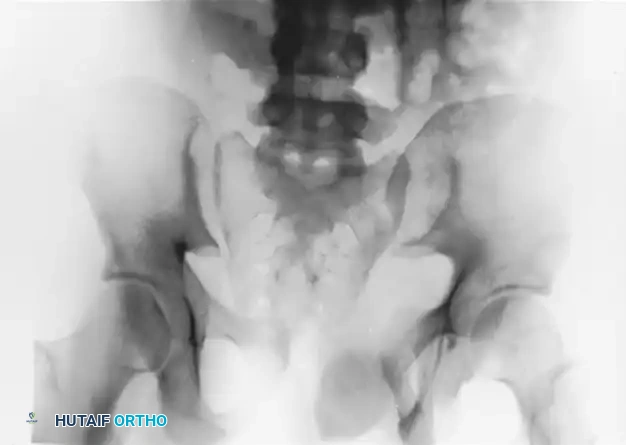

FIGURE 56-46 A-D: Young and Burgess lateral compression type III (LC III) injury with marked displacement of the right pubic ramus. Preoperative anteroposterior, inlet, outlet views, and CT scan demonstrate the severe rotational instability.